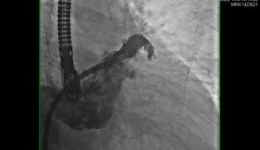

• 徐医附院心内科完成第一例经皮左心耳封堵术

徐医附院心内科完成第一例经皮左心耳封堵术

徐州医科大学附属医院心血管内科于2017年7月18日成功完成第1例经皮左心耳封堵术。该术式是目前国际上预防房颤病人卒中的最新方法,2013年起正式在我国开展,目前国内仅有北京、上海、湖北等少数地方开展。病情介绍患者袁某,男性,69岁,此次因“突...